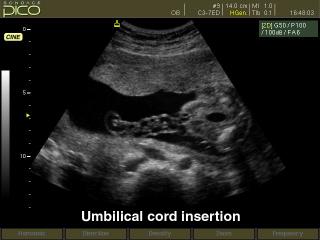

- CFM - цветное допплеровское картирование;

- PD - энергетический допплер;

- PW - импульсный допплер;

- дуплексный и триплексный режим; трапецевидный режим сканирования для линейных датчиков. - Кардиопакет для исследования сердца плода (входит в базовую комплектацию).

- CAFE (Compound Automatic Flash Elemination) - обеспечивает зависимую от используемого режима нелинейную фильтрацию для удаления цветных точек на изображении, возникающих из за мерцающих артефактов. Создает улучшенную визуализацию кровотока во всех допплеровских режимах.

Акушерские исследования (плод, сердце плода), гинекология (матка, яичники), абдоминальные исследования (печень, желчный пузырь, поджелудочная железа, селезенка, глубокие сосуды), почки.